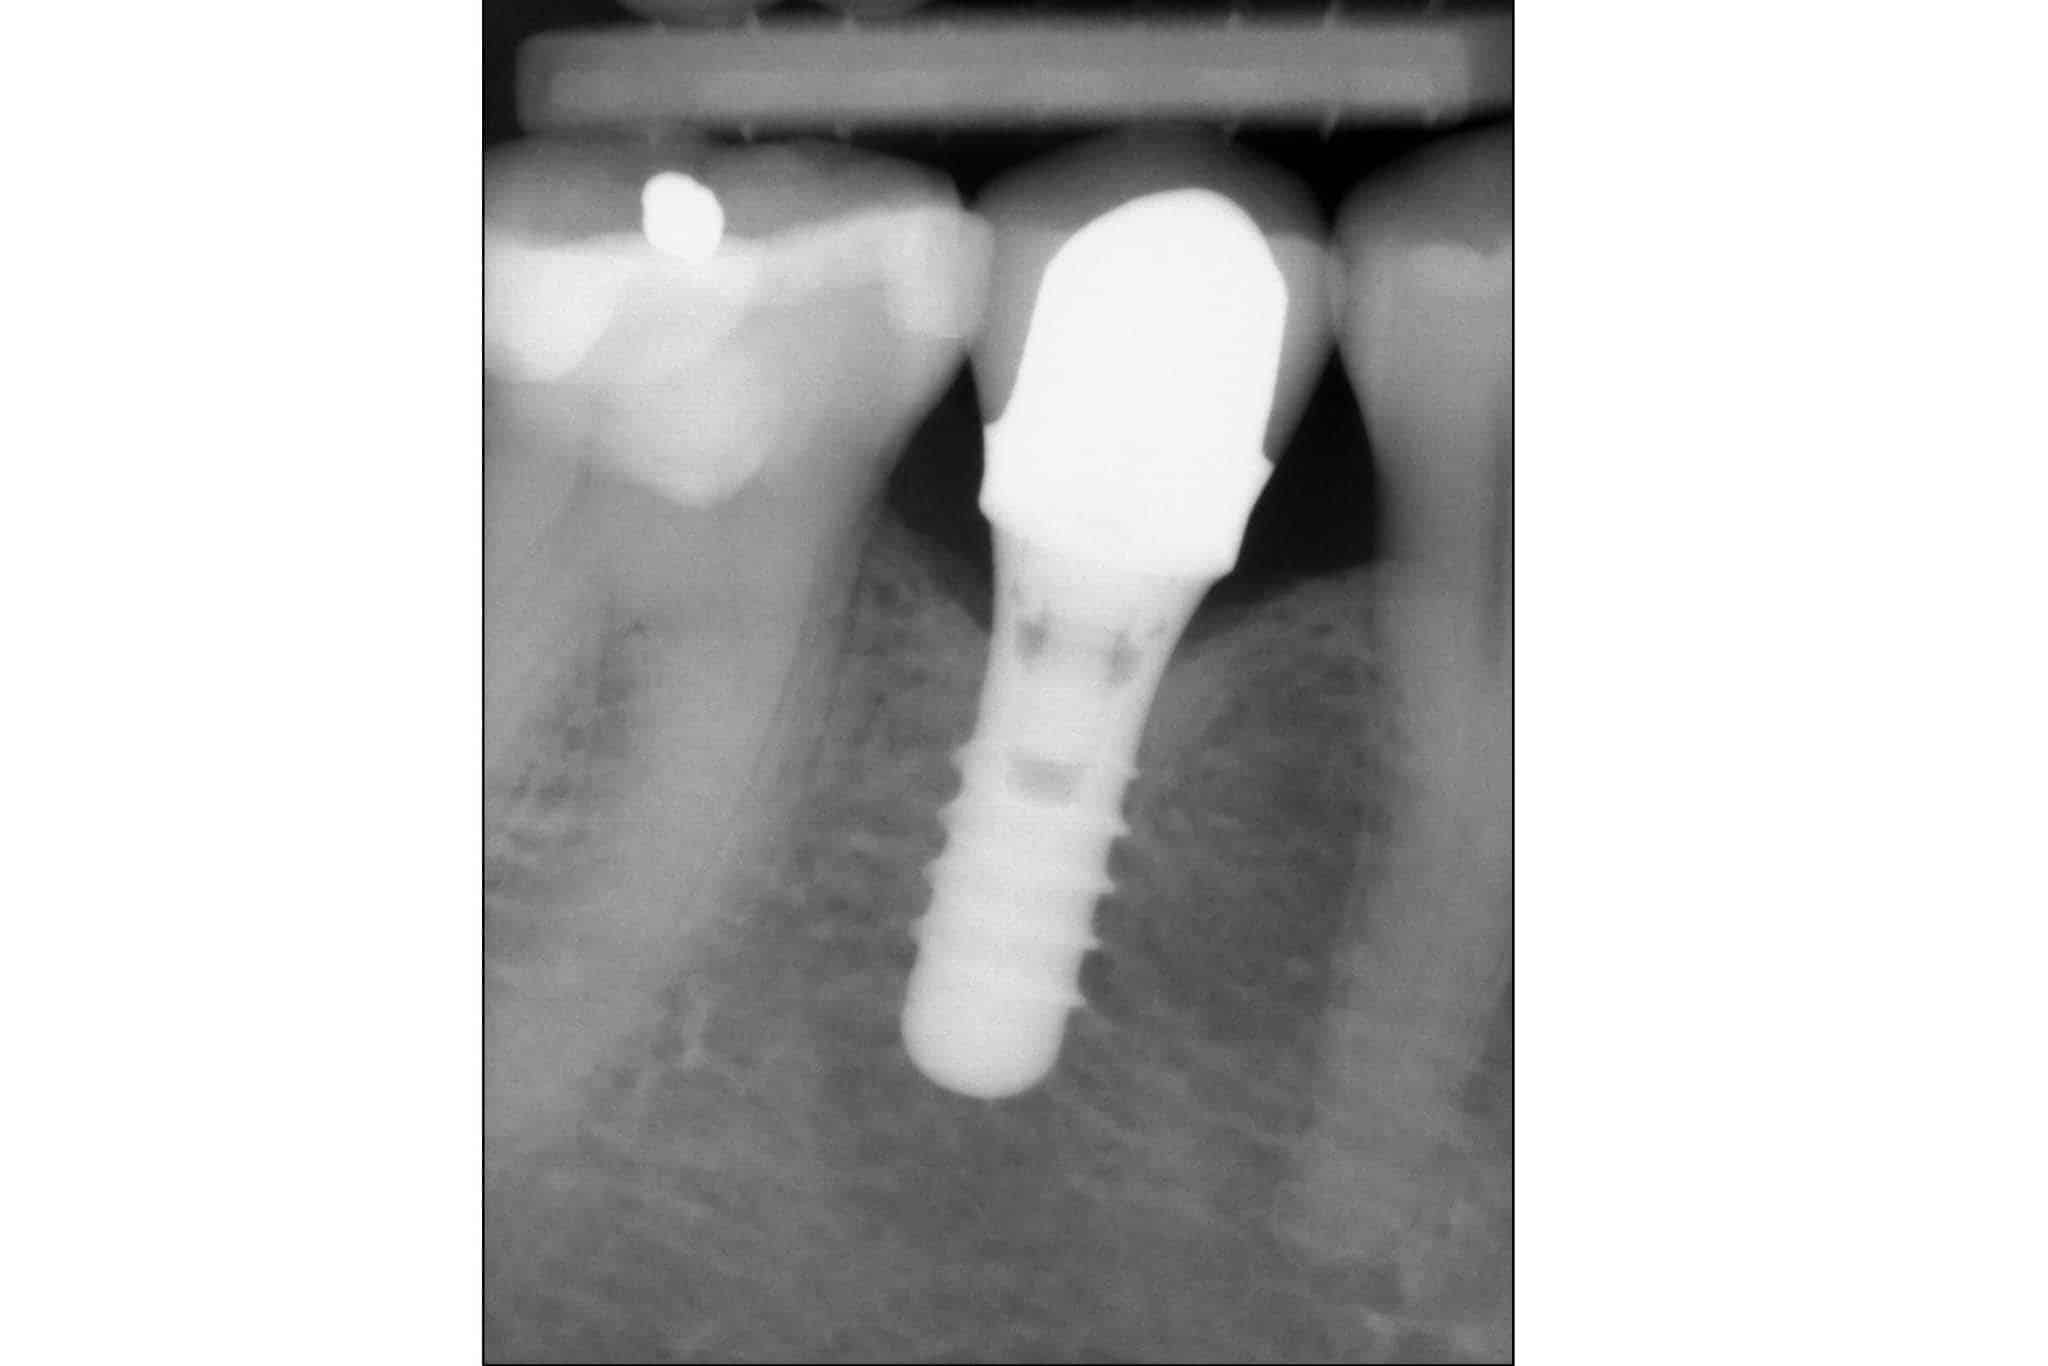

Bildet viser midtre tann som implantat – sammenligning av foto og røntgen.

Før- og etterbilder av tannimplantater – Se våre pasientresultater

Bildet viser resultat før og etter tannimplantat.

Resultat av implantatbehandling dokumentert på foto og røntgen.

Resultat etter tannimplantat.